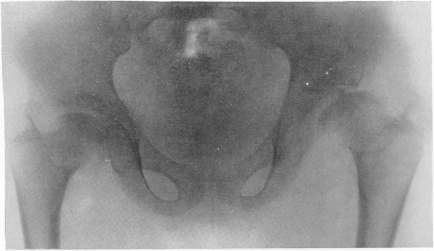

Fig. 277. Același pacient. Radiografia pelvisului. Modificări tipice ale capului femural, care amintesc de osteochondropatie.

Deformarea semnificativă a varusului. Copilului i se face referire la examinarea radiologică în legătură cu tulburarea în ultimul an: a fost suspectată coxita tuberculoasă unilaterală.